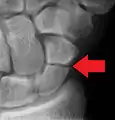

Radiolucency around a 12 days old scaphoid fracture that was initially barely visible.[13]

Scaphoid fractures are often diagnosed using plain radiographs and multiple views are obtained as standard.[9] However, not all fractures are apparent initially.[7] In 1/4 of cases, the clinical examination suggests a fracture, but the X-ray does not show it, even though there is indeed a fracture.[10] Therefore, people with tenderness over the scaphoid (those who exhibit pain to pressure in the anatomic snuff box ) are often splinted in a thumb spica for 7–10 days at which point a second set of X-rays is taken.[7] If a minimally displaced fracture was present initially, healing will now be apparent. Even then a fracture may not be apparent. A CT Scan can then be used to evaluate the scaphoid with greater resolution. The use of MRI, if available, is preferred over CT and can give one an immediate diagnosis.[11] Bone scintigraphy is also an effective method for diagnosis fracture which do not appear on Xray.[12]